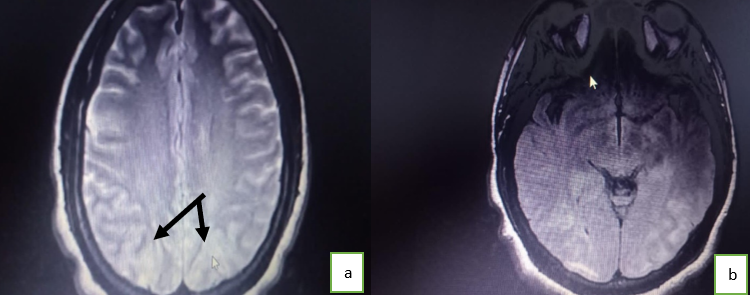

Nous avions évoqué devant ce tableau une thrombose veineuse cérébrale et/ou un accident vasculaire cérébral, sans écarter une encéphalopathie hypertensive. Le dosage des D-dimères négatif avait permis d’éliminer une thrombose veineuse cérébrale. Le scanner cérébral était normal. L’IRM (Imagerie par Résonnance Magnétique) cérébrale mettait en évidence un hypersignal T2 Flair et hypersignal ADC pariéto-occipital bilatéral en faveur d’une encéphalopathie postérieure (figure 1). La patiente a reçu du phénobarbital et de la nicardipine par voie parentérale. L'évolution clinique a été favorable, avec une récupération de ses déficits neurologiques en quelques jours, un amendement des convulsions et des céphalées, et une régularisation de la pression artérielle.

Radiologiquement, l’examen clef pour poser ce diagnostic est l’IRM cérébrale (11). Le scanner cérébral réalisé initialement avait été non contributif. La littérature rapporte que la TDM cérébrale est un moyen de diagnostic mais moins sensible. Elle peut être normale comme observée chez notre patiente, ou montrer des lésions hypodenses cortico-sous-corticales. Typiquement, l’IRM retrouve des anomalies corticales et sous-corticales d’oedème vasogénique (en hyper-signal T2 et FLAIR) prédominantes dans les régions pariéto-occipitales (figures 1 et 2).

Figure1 : IRM cérébrale : Hypersignal T2 pariétal occipital (a), Hypersignal Axial T2 flair pariétal occipital (b).